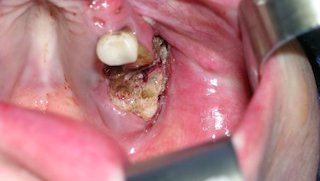

Osteonecrosis of the jaw: Treating bone loss triggered by drugs for osteoporosis, cancer

Osteonecrosis of the jaw is a rare effect of antiresorptive drugs for osteoporosis and cancer. But early, specialized dentistry and oral surgery can cure it.